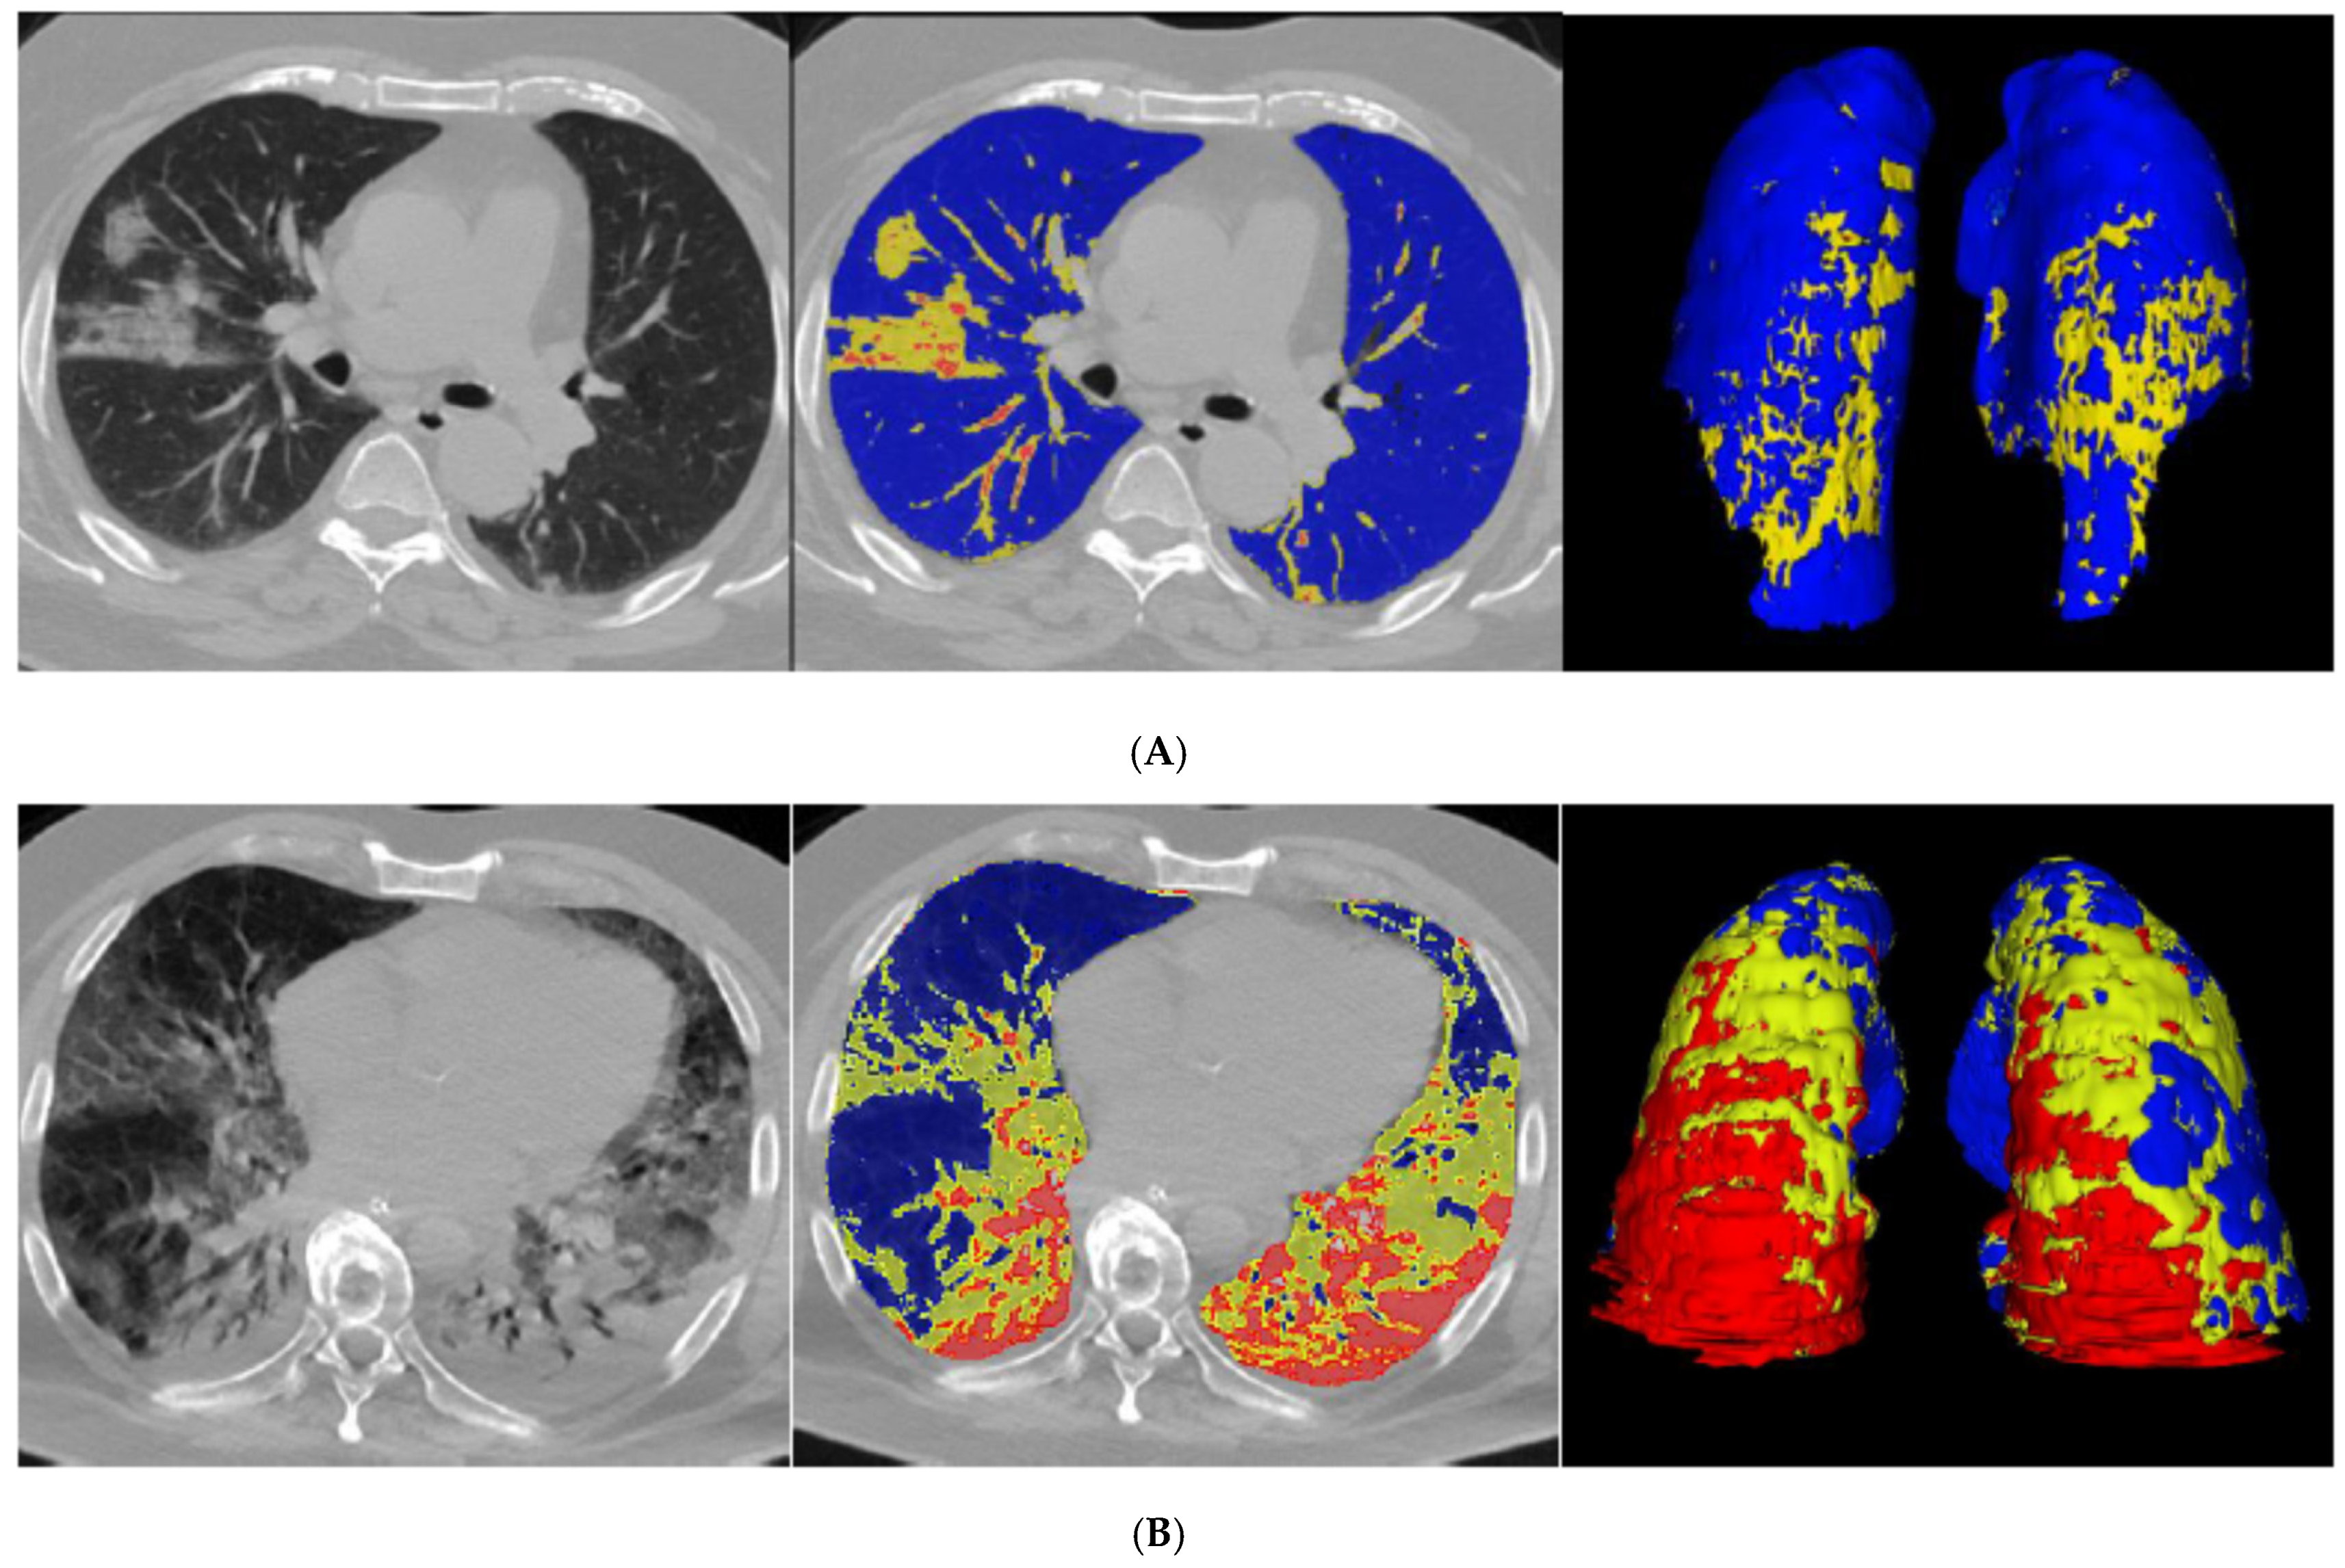

All CT scans were of satisfactory quality for analysis. Case examples of QCT with %CL < or >23% and different texture between %PAL and %NNL are illustrated in Figure 1. Median %CL was 16% in the deceased group (IQR, 10–32%) and 11% in the recovered group (IQR, 6–19%). The difference proved statistically significant (p < 0.001; Table 2).

Figure 1.

Unenhanced CT scan and QCT analysis in four patients with COVID-19 pneumonia. (A,B) show one QCT with %CL < 23% and one with %CL > 23%. (C,D) highlight the texture differences between the “poorly aerated” volume (%PAL, −500, −100 HU) and “non-aerated” volume (%NNL, 100, -100 HU). (A) refers to a 71-year-old man, oxygenated through nasal cannulae. Upon admission, laboratory tests were as follows: D-dimer 199 ng/mL, fibrinogen 416 mg/dL, PT ratio 1.03, CRP 1.0 mg/dL. %CL was 10%. Non-contrast axial chest CT showed ground-glass opacities, predominantly in the middle lobe; quantitative analysis highlights poorly aerated lung volumes in yellow (8% PAL) and normally aerated lung volumes in blue. (B) refers to a 64-year-old man who required mechanical ventilation and intubation. Upon admission, laboratory tests were as follows: D-dimer 1161 ng/mL, fibrinogen 1021 mg/dL, PT ratio 1.18, CRP 45.3 mg/dL. %CL was 55%. Non-contrast axial chest CT showed diffuse bilateral ground-glass opacities and posterior lung consolidation; quantitative analysis highlights non-aerated lung volumes in red (19% NNL), poorly aerated lung volumes in yellow (36% PAL), and normally aerated lung volumes in blue. (C) refers to a 65-year-old woman who required mechanical ventilation and intubation. Upon admission, laboratory tests were as follows: PT ratio 1.34, CRP 31.9 mg/dL. %CL was 66%. Non-contrast axial chest CT showed extensive posterior consolidation of the right lower lung lobe and patchy dense consolidation in the subpleural space of both left lower and upper lung lobes; quantitative analysis highlights poorly aerated lung volumes in yellow (23% PAL) and non-aerated lung volumes in red (43% NNL). (D) refers to a 66-year-old man who required mechanical ventilation and intubation. Upon admission, laboratory tests were as follows: D-dimer 1335 ng/mL, fibrinogen 832 mg/dL, PT ratio 1.20, CRP 33.8 mg/dL. %CL was 62%. Non-contrast axial chest CT showed extensive ground-glass consolidation with “crazy paving” pattern typical of COVID-19; quantitative analysis highlights normally aerated lung volumes in blue, non-aerated lung volumes in red (12% NNL), and poorly aerated lung volumes in yellow (50% PAL).